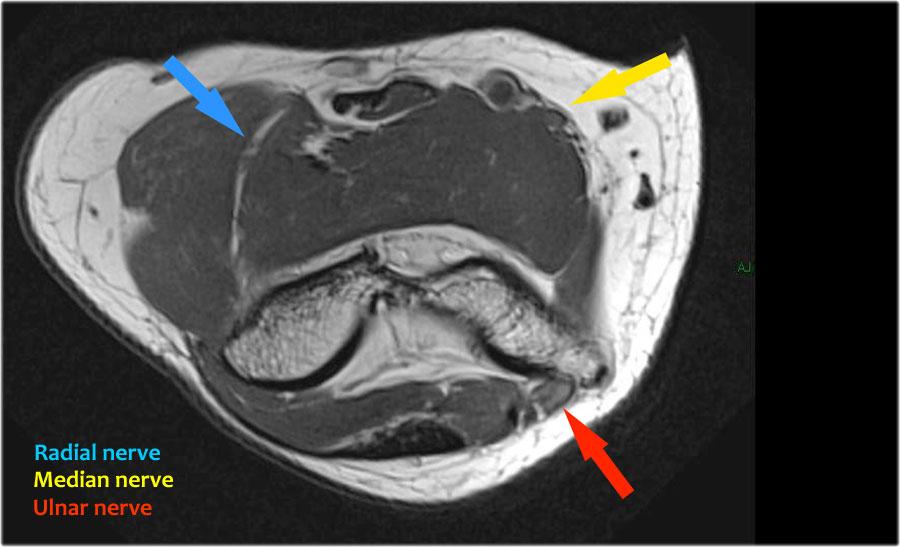

Nerves

Scroll through the images.

Ulnar nerve

Ở đây chúng ta thấy dây thần kinh trụ nằm trong ống trụ.

Bó sau của dây chằng bên trụ tạo thành sàn của ống, trong khi mạc hãm tạo thành trần của ống.

Radial nerve

Dây thần kinh quay có thể được xác định rõ nhất ở mức chỏm xương quay, nơi có thể quan sát thấy các nhánh nông và nhánh sâu trong ống xương quay (mũi tên).

This is a very consistent place to find the radial nerve.

Các nhánh quay sâu tạo thành thần kinh gian cốt sau xuyên qua cơ ngửa tại cung Frohse (mũi tên).

Median nerve

Dây thần kinh giữa đi xuống phía sau Lacertus fibrosis, là cân cơ của cơ nhị đầu và xuyên qua cơ sấp tròn.